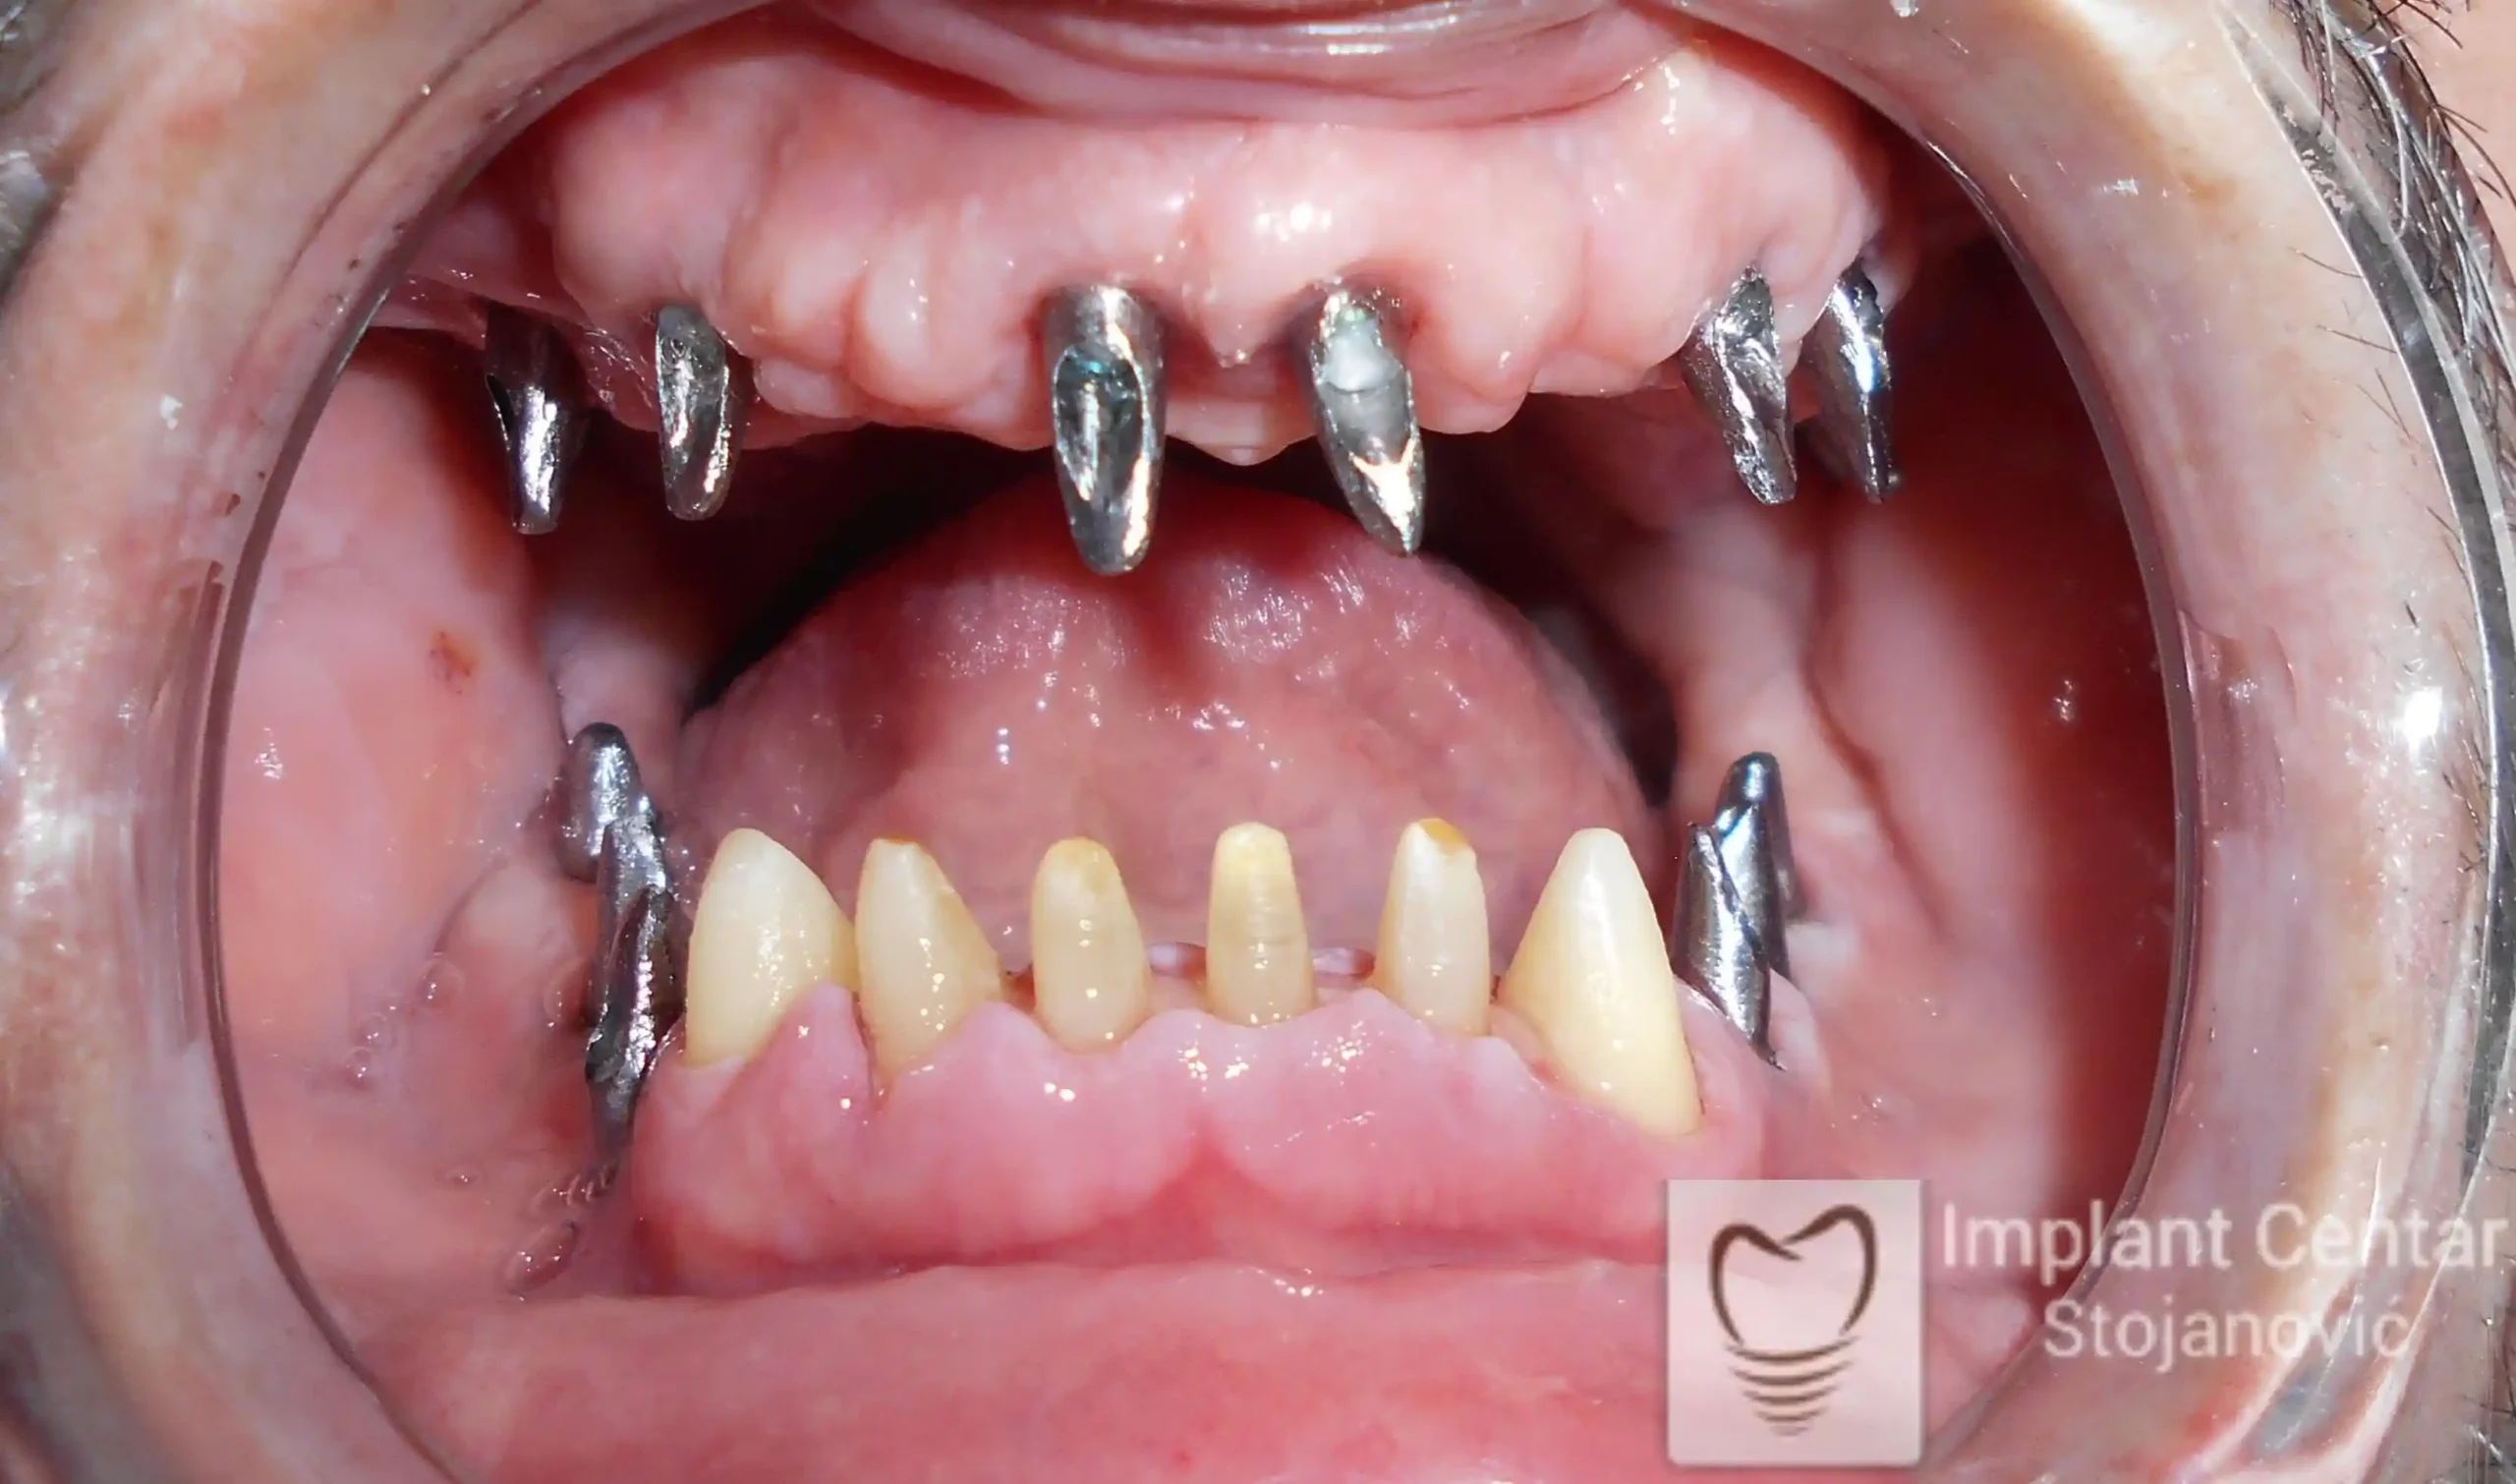

Pacijent sa rascepom usne, nepca i alveolarnog grebena uspešno je rehabilitovan fiksnim protetskim radom na implantatima. Pre dolaska u našu ordinaciju, pacijent je u gornjoj vilici nosio totalnu protezu preko preostalih zuba, dok je u donjoj vilici bio zbrinut parcijalnom mobilnom protezom. Tokom višegodišnje potrage za adekvatnim rešenjem, pacijent nije uspeo da pronađe zadovoljavajuću terapijsku opciju ni u zemlji ni u inostranstvu.

Nakon detaljnog kliničkog pregleda i analize radioloških snimaka, izrađen je sveobuhvatan plan terapije sa ciljem uklanjanja mobilnih proteza i postizanja maksimalne funkcionalne i estetske rehabilitacije. Zbog loše biološke vrednosti preostalih zuba, doneta je odluka o njihovom vađenju i ugradnji dentalnih implantata.

Poseban terapijski izazov predstavljalo je premošćavanje defekta nastalog usled rascepa, kao i ograničena količina raspoložive kosti u gornjoj vilici. Primenom većeg broja implantata i odgovarajućih procedura nadoknade kosti, postignuta je stabilna osnova za fiksni protetski rad.

Tokom perioda oseointegracije, pacijent je bio zbrinut fiksnim privremenim krunicama, čime je već pet dana nakon intervencije obezbeđena potpuna funkcionalna i estetska rehabilitacija. Nakon završetka perioda integracije implantata, izrađeni su definitivni cirkonijum-keramički mostovi na implantatima.